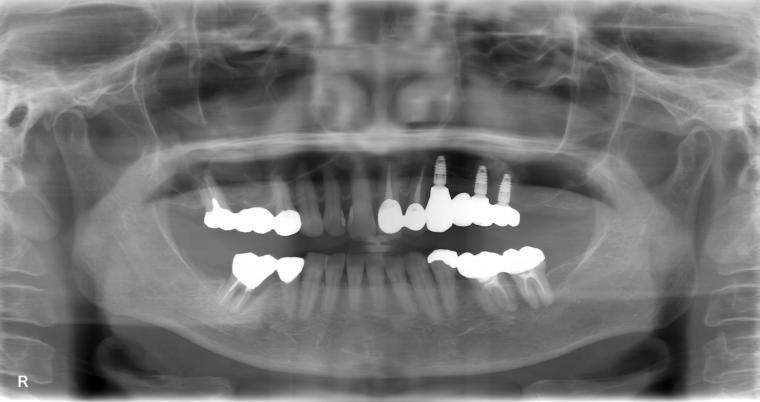

AFTER

65歳女性/上3本欠損/インプラント埋込手術

インプラントでの治療を選択されました。

現在も定期検診で拝見させていただいています。